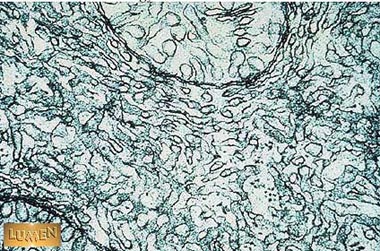

What kind of hormone would this cell secrete?

Steroid